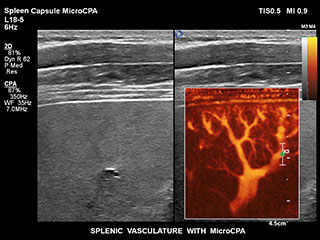

Bisher war die Erfassung von Flussdaten bei kleinen Gefässstrukturen mit niedriger Flussrate schwierig. Die neue EPIQ Funktion MicroCPA bietet eine schnelle und einfache Darstellung von Mikrozirkulation mit niedriger Geschwindigkeit und ermöglicht eine hohe Diagnosesicherheit bei der Beurteilung der Organperfusion oder von kleinen Gefässbetten.